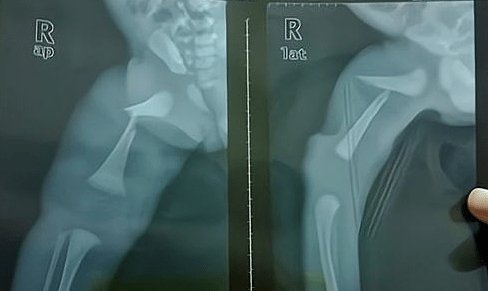

2、怎么看小孩有没有骨折图片